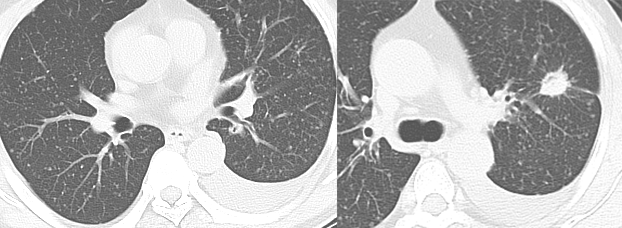

乳腺癌空洞性肺转移。

54 岁男性,肾癌病史。左肺下叶厚壁空洞性转移(穿刺证实),左肺另见不伴空洞的实性小结节转移灶。

男,63 岁。食管鳞癌术后 3 年,痰中带血丝半年。穿刺证实双肺多发空洞和空泡转移,周围磨玻璃密度是转移瘤引起出血。